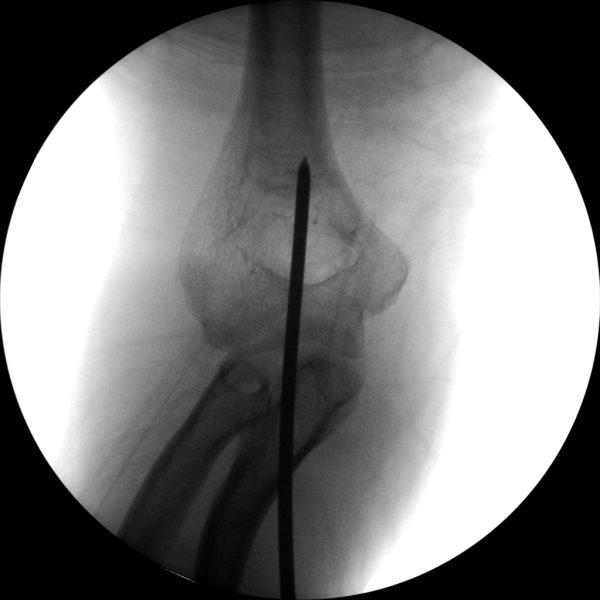

Skan-C plays a critical role in orthopaedic procedures, providing excellent imaging during interventional procedures, and allowing for precise localization and accurate treatment. The ability of Skan-C to offer dynamic visualization of visualization structures enhances patient safety, minimizes complications, and improves the overall effectiveness of orthopedic interventions.

Orthopedic procedures in which Skan-C is highly effective are

CRIF - Closed reduction internal fixation

ORIF - Open reduction internal fixation